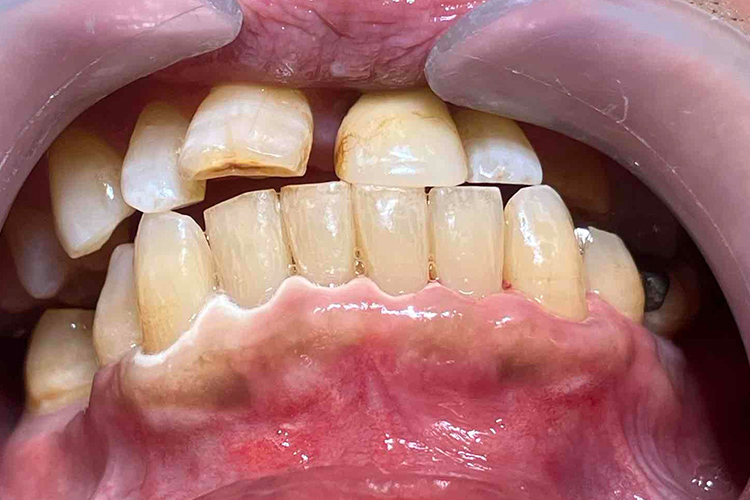

“実際の実施例1”

この患者様は、口腔内全体において重度の歯周病が生じており、歯磨き指導、クリーニング、Flap手術等を行ったが、歯周ポケットが深すぎるため、ブルーラジカル適用症例と診断し、施術を行いました。

(実施前)

施術前のレントゲンと口腔内写真です。施術前にプラークの除去を行ってから、施術します。